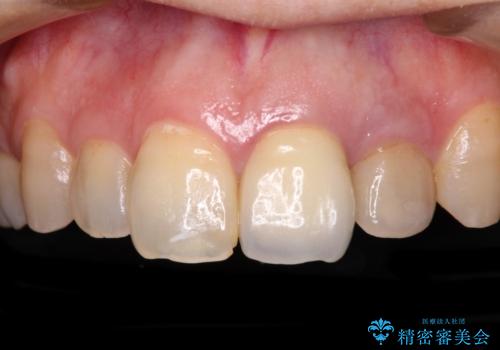

真ん中のオールセラミッククラウンを正面から見ると大変自然に仕上がっているのですが、側方から見ると白色が強く、さらには隣の歯は神経が除去されて変色していたため、コントラストでより色の違いが際立っていました。

前歯2本をオールセラミッククラウンにて補綴治療することとしました。